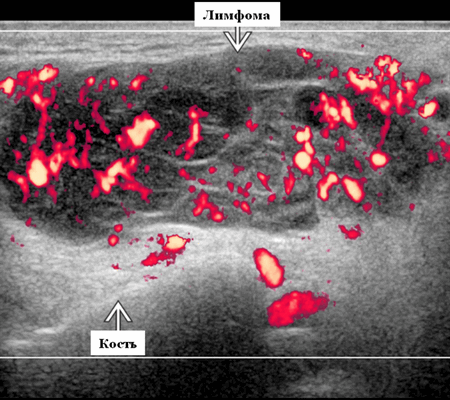

Цветной допплер. Узловая НХЛ. Выраженная центральная или внутриузловая гиперваскуляризация. Паренхима при неходжкинской лимфоме более диффузная железистая гиперваскуляризация. Васкуляризация от умеренной до выраженной в плохо очерченных образованиях.

- Цветной допплер: смешанная васкуляризация с выраженным сосудистым рисунком и наличием периферической васкуляризации. Периферическая сосудистая сеть редко встречается в узлах НХЛ

Цветовой допплер: смешанная сосудистая сеть с выраженными внутриузловыми сосудами и наличием периферической сосудистой системы. Одна только периферическая сосудистая сеть редко встречается в узлах НХЛ. Спектральный допплер: переменное интранодальное внутрисосудистое сопротивление, которое носит неспецифический характер.